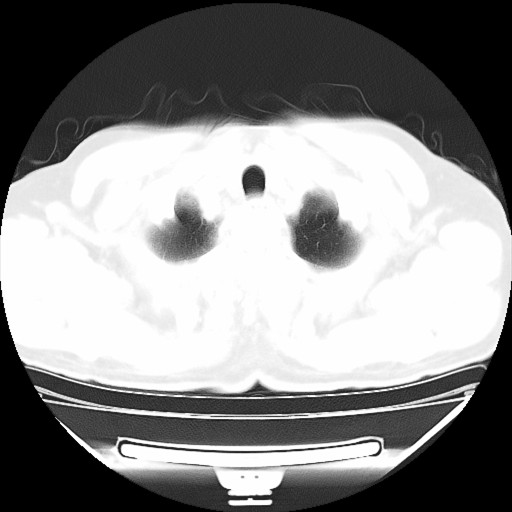

以下是引用hhcckk在2009-5-29 10:34:00的发言:[br]左下肺片絮状边缘模糊影,考虑感染,建议治疗后复查[br]